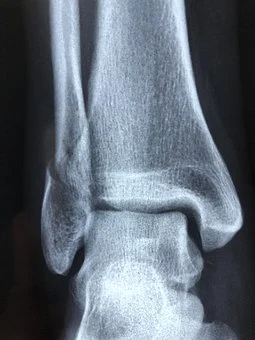

골절은 방사선 검사에 의해서 확진되지만, 신체 검진을 통하여 확인할 수도 있습니다. 골절 부위를 움직였을 때 통증과 함께 골편의 마찰로 인해 발생하는 염발음(뼈가 서로 마찰되면서 생기는 소리)을 확인할 수도 있습니다.